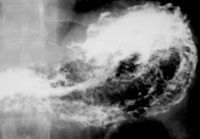

(3)X線胃腸鋇餐檢查可確診。

可見可變的十二指腸球底部中心性充盈缺損,典型病例可見幽門管增寬,胃黏膜皺襞通過幽門管進入十二指腸球部,使十二指腸球部呈“蕈狀”或“降落傘”狀變形。